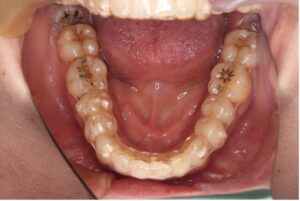

マウスピース矯正は透明の装置を歯にはめて歯を動かす方法です。

目立ちにくく、自身で取り外しができることが特徴です。

取り外しが可能なため普段と変わらず食事ができる、歯磨きがしやすく虫歯や歯周病のリスクを抑えやすいという点が魅力です。

だだし、裏を返せば外せてしまうということがデメリットでもあります。

1日20〜22時間装着する必要があるため、外している時間が長いと歯は動きません。

自己管理がポイントになってきます。

〈メリット〉

・目立ちにくい

・取り外しができるため口腔内を清潔に保ちやすい

・口内炎ができにくい

・ワイヤー矯正より通院回数が少ない(1〜2ヶ月に一回来院)

〈デメリット〉

・自己管理が必要

・症例によってはワイヤー治療を併用することがある